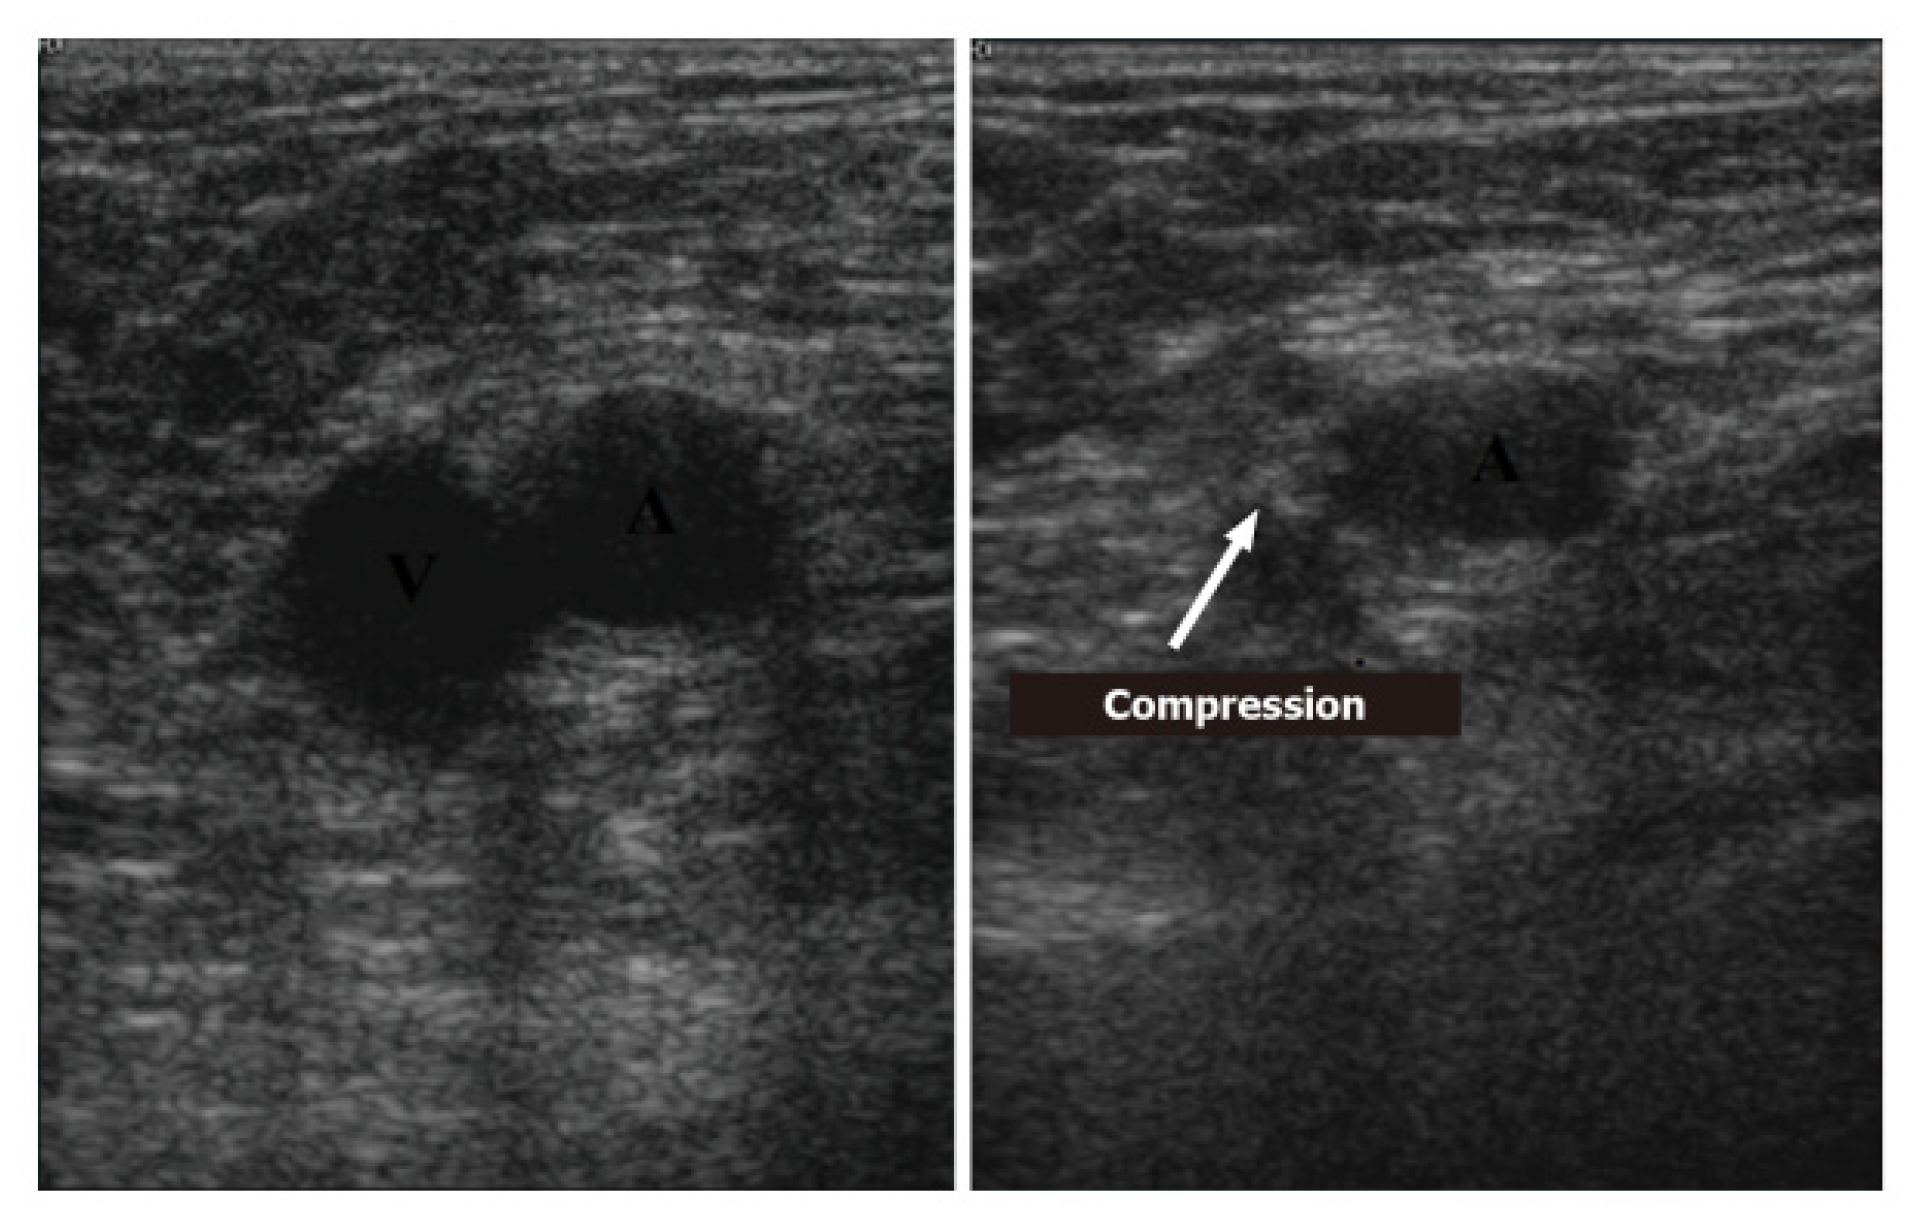

5. Deep-Vein Thrombosis

5.1. Protocol

5.2. Imaging

- Acute: the thrombus itself may not be visible. If detected, it is deformable with the force applied on the probe and with a regular surface; it is a distended vein.

- Subacute thrombus: (before six months and after clot formation) intermediate morphological changes that cannot be included in the chronic phase.

- Chronic post-thrombotic change: not compressible nor deformable with an irregular surface; the vein caliber may be normal or reduced.

- Di Vilio, A.; Vergara, A.; Desiderio, A.; Iodice, F.; Serio, A.; Palermi, S.; Gambardella, F.; Sperlongano, S.; Gioia, R.; Acitorio, M.; et al. Incremental value of compression ultrasound sonography in the emergency department. World J. Crit. Care. Med. 2021, 10, 194–203. [Google Scholar] [CrossRef]